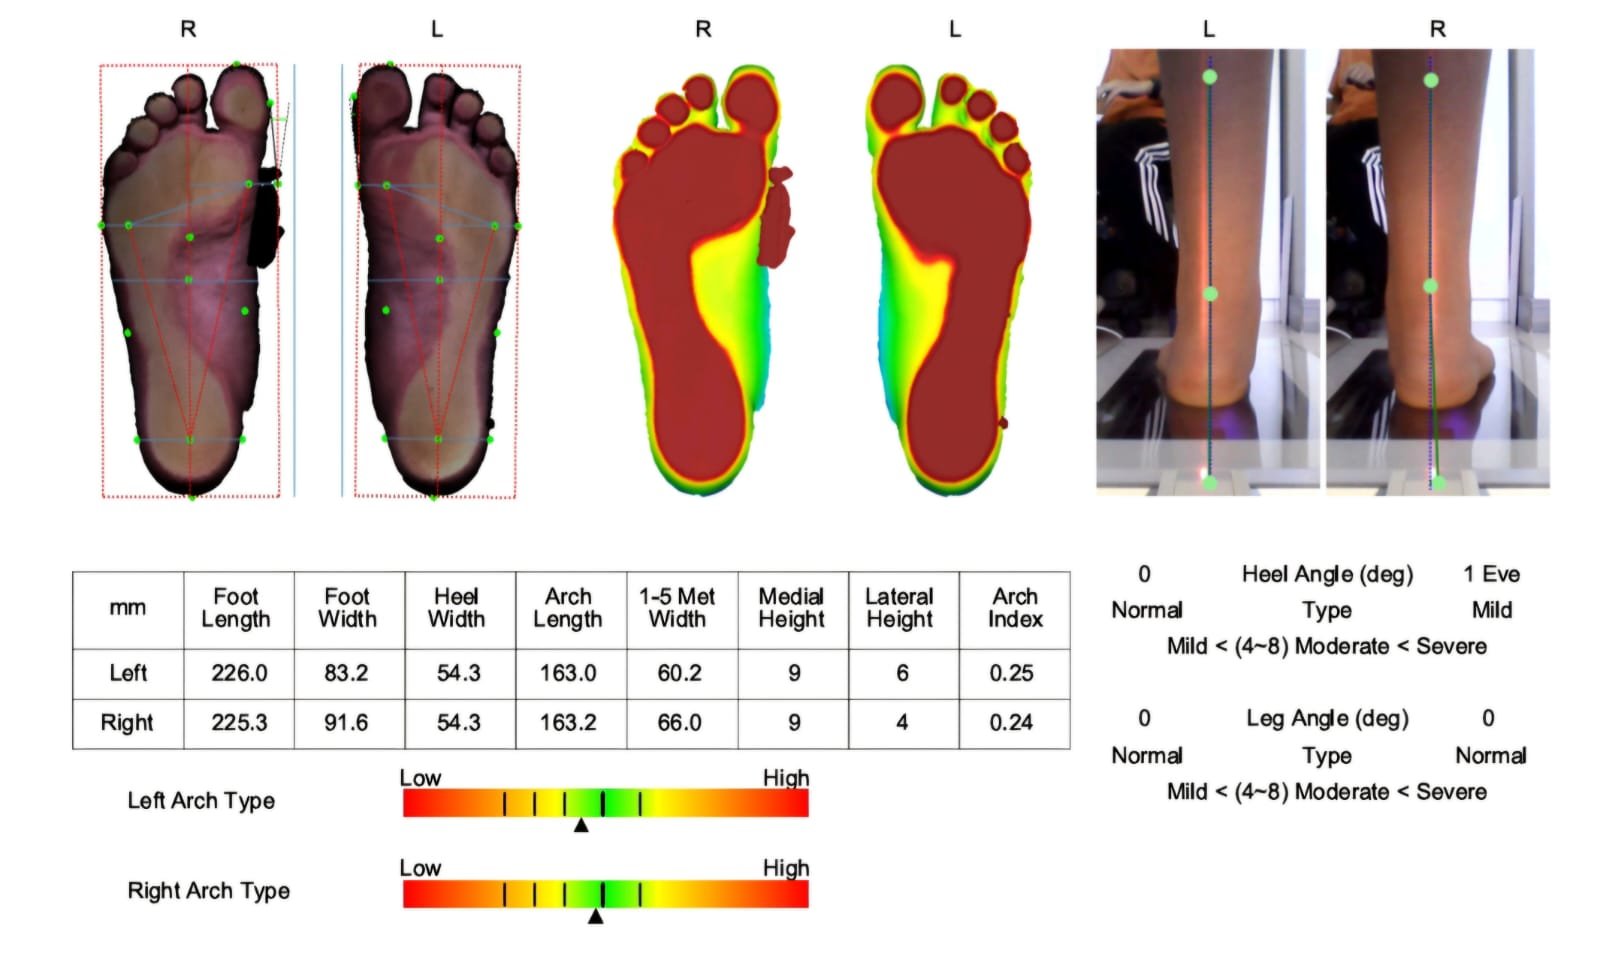

Con nuestro footscan 3D, analizamos tu huella plantar, detectando alteraciones como pie plano, cavo o mixto.